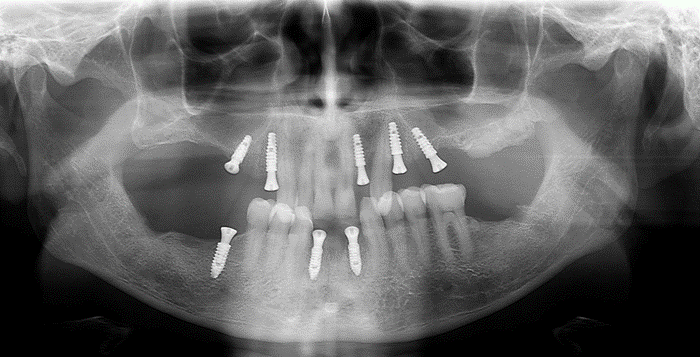

Um paciente procurou tratamento protético reabilitador com queixa dos dentes 31 e 41 que estavam abalados. Ao exame clínico e radiográfico, notou-se mobilidade dos dentes, doença periodontal ativa e perda óssea.

Avaliamos o espaço mésio-distal entre os dentes 33 e 43 e constatamos a ausência de distância para a colocação de implantes individualizados. Assim sendo, optamos pela instalação de dois implantes Veloce CM de diâmetro 3.3 e pilares do tipo micro-cônico para a solução clínica.

Dessa forma, na matéria desta semana, será abordada uma situação clínica de espaço mésio-distal restrito com o uso de implantes híbridos do tipo Veloce CM estreitos de 3.3 de diâmetro e posterior confecção de prótese sobre implantes com pilares intermediários do tipo micro-cônico.

Diante do caso clínico apresentado, constatamos a importância de um correto planejamento, que evidenciou a necessidade de implantes estreitos do tipo Veloce CM e sobre esses implantes os componentes também estreitos do tipo micro-cônico para que os espaços desdentados mésio-distais fossem respeitados de forma adequada.

– em casos de espaço mésio-distal restrito podemos lançar mão de implantes estreitos do tipo Veloce de diâmetro 3.3;

– para seguir a mesma linha de raciocínio, os componentes também devem ter uma plataforma reduzida para poder assentar adequadamente a prótese sobre os implantes e o componente escolhido foi o micro-cônico.